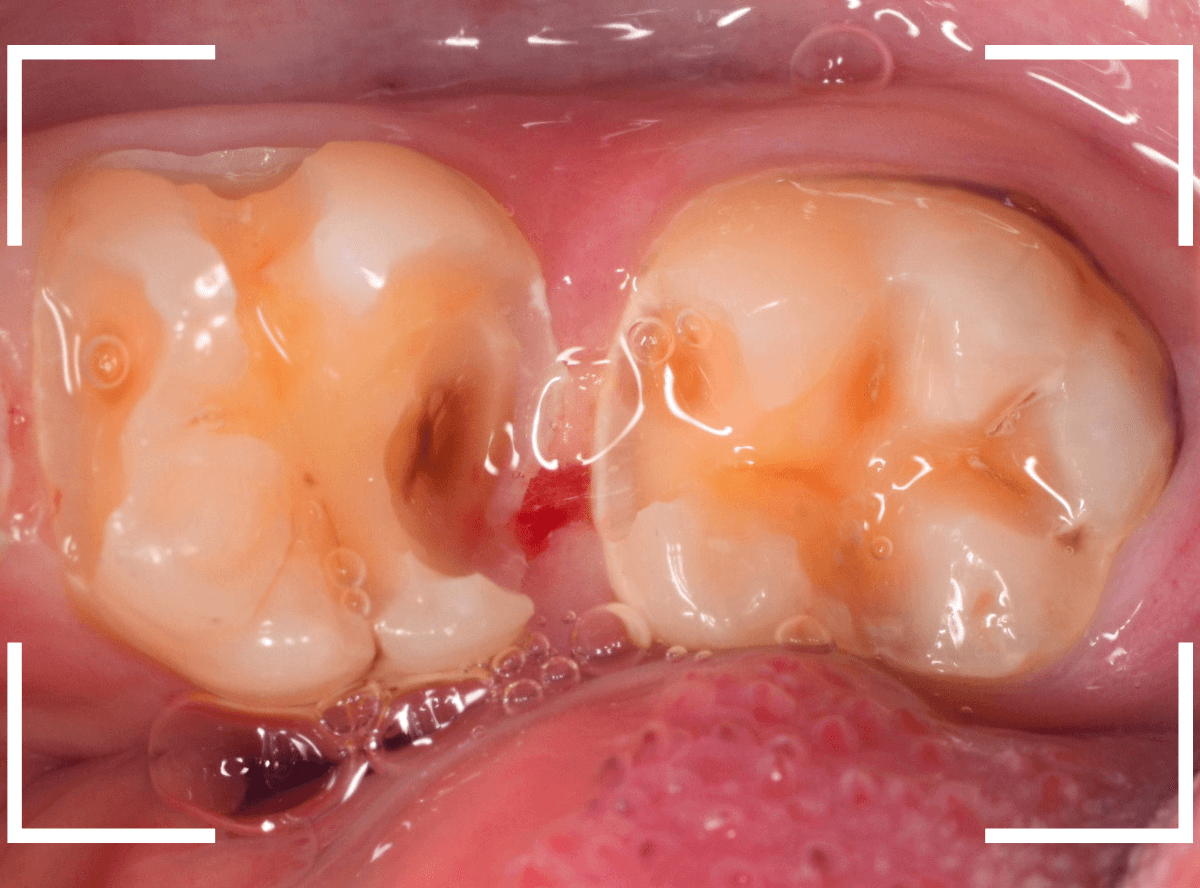

Case.18 2本に渡る大きな虫歯

「歯に大きな穴が開いていて痛い」という訴えで来院された患者さんです。

金属のつめものの脇に大きな穴が開いているのがわかります。

レントゲン写真で確認します。

赤い線が虫歯、青い線が神経です。

奥歯も神経に到達しそうな、大きな虫歯になっているのがわかります。

早めの治療が必要です。

セメントも除去したところです。

両歯とも、とても大きな虫歯なのがわかります。